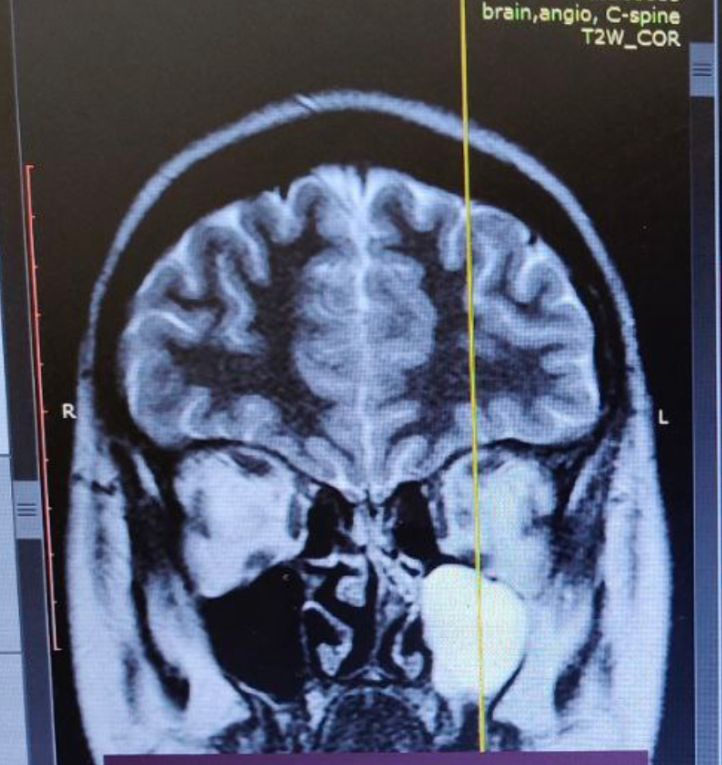

сейчас невролог ведёт меня. Консультирует но пока проблемы не нашли, сделала мрт головного мозга,артерии и Вены мозга.и шейный отдел

в заключениях не было ничего по этому снимку - но невролог увидела это. Одна пазуха забита чем-то. сказала записаться к Лору, записалась - но записей много. Придётся ждать

по этому снимку выдает кисту с таким же снимком